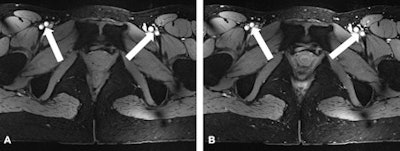

Increasing RF inhomogeneity with increasing field strength also posed challenging, as inadequate homogeneity of the RF magnetic field impairs the generation of accurate refocusing pulses, which are a prerequisite for high-quality TSE imaging.

"To mitigate the effects of these variations in magnetic field uniformity, dedicated B1 shimming was performed with a custom eight-channel RF shimming setup to reduce B1 artifacts in the region of interest," the researchers wrote. "Nevertheless, minor impairment due to variations in B1 uniformity remained as demonstrated in mild differences in anterior versus posterior fat signal intensities; these might be addressed with an RF shimming system with a higher degree of freedom in future studies."